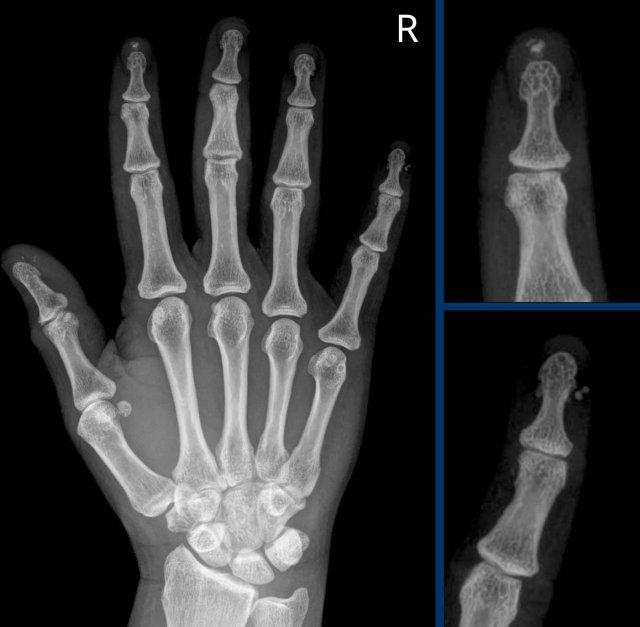

Các ví dụ điển hình về các dạng bào mòn đặc trưng

- Viêm khớp dạng thấp.

Bào mòn bờ khớp điển hình tại các khớp MCP. - Viêm xương khớp bào mòn.

Bào mòn xương dưới sụn tại các khớp DIP và PIP. Sự hình thành đồng thời của gai xương tạo ra biến dạng cánh hải âu. - Bệnh gout.

Bào mòn lệch tâm với bờ nhô ra. Bờ xơ cứng trong trường hợp này cho thấy bệnh mạn tính và tiến triển chậm. - Nhiễm trùng.

Tổn thương phá hủy kèm mất sụn và bào mòn xương. - Viêm khớp vảy nến.

Bào mòn xương thu hẹp đầu đốt ngón gần thành hình “bút chì”, tựa vào “cốc” được tạo bởi nền đốt ngón xa mở rộng do tăng sinh xương. - Xơ cứng bì.

Và các rối loạn đa hệ thống khác có thể gây bào mòn tại các chỏm đốt ngón xa, tình trạng này được gọi là tiêu xương đầu chi (acro-osteolysis).

Hình ảnh bào mòn xương vùng rìa điển hình và hẹp khe khớp tại các khớp MCP 3-5.

Lưu ý hình ảnh hẹp khe khớp đồng đều tại các khớp MCP.

Các khớp liên đốt gần (PIP) chỉ biểu hiện hẹp khe khớp tối thiểu.

Đây là trường hợp viêm khớp dạng thấp giai đoạn cuối với các thay đổi bào mòn nặng nề và đứt dây chằng gây trật khớp tại các khớp MCP.

Phân ly xương thuyền – xương nguyệt (mũi tên trắng) là dấu hiệu thường gặp do tình trạng viêm lan tỏa khối xương cổ tay. Cả tình trạng phân ly lẫn viêm đều có thể gây hẹp khe khớp quay – cổ tay.

Lưu ý hình ảnh bào mòn xương đầu dưới xương trụ kèm theo sưng nề phần mềm xung quanh (mũi tên xanh).

Trong trường hợp viêm khớp dạng thấp này, có hình ảnh bào mòn xương vùng rìa liền kề với hầu hết các khớp bàn ngón chân (MTP) (đầu mũi tên).

Khớp MTP thứ 5 là khớp bị tổn thương thường xuyên nhất trong viêm khớp dạng thấp.

Khi tình trạng bào mòn nặng nề như trong trường hợp này, hình ảnh có thể trông giống biến dạng “bút chì trong cốc” (mũi tên trắng) – dấu hiệu thường gặp trong viêm khớp vảy nến.

Tuy nhiên, phân bố tổn thương chủ yếu ở các khớp MTP và ít ảnh hưởng đến các khớp liên đốt là dấu hiệu gợi ý đây là trường hợp viêm khớp dạng thấp.